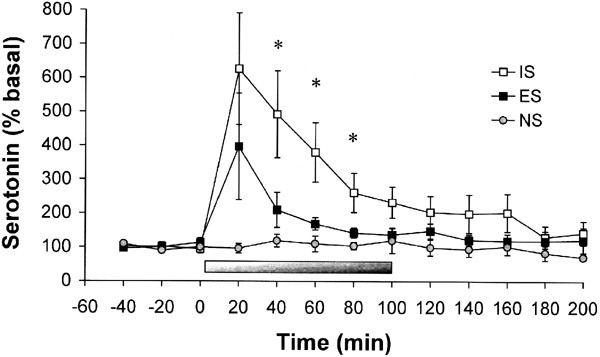

5-HT efflux increased significantly during IS compared to ES and NS (Figure 2). This was demonstrated by a significant main effect of Group, F(2,20)=13.73, p<0.01. Post hoc tests indicated that IS was different from ES and NS, and no other group differences were found. There was a significant main effect of Time, F(12,240)=6.46, p<0.01, reflecting an increase in 5-HT during stress. This increase was greatest in IS rats, indicated by a significant Group × Time interaction, F(24,240)=2.41, p<0.01. Simple effects tests indicated that IS was different from ES and NS at 40, 60, and 80 min, and from NS at 100 and 120 min, all p<0.05. There were no significant effects of Hemisphere on 5-HT efflux (data not shown).

Figure 2

5-HT efflux (expressed as a percentage of baseline) in the mPFC before, during, and after exposure to IS, ES, or NS. The bar indicates the duration of the stress session. Exposure to IS selectively increased 5-HT efflux in the mPFC during the stress session. Data are means±SEM for nine rats per group. *IS significantly different from ES and NS at this time point, p<0.05.